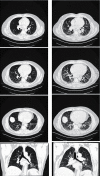

Interstitial lung disease (ILD) associated with connective tissue diseases (CTDs) is highly heterogeneous in its clinical presentation and course. The diagnosis and management of CTD-ILD require a multidisciplinary approach involving, at minimum, a rheumatologist, a pulmonologist, and a radiologist. Close monitoring of patients with CTD-ILD is important to enable early detection of disease progression and inform decisions regarding the initiation or escalation of pharmacotherapy. In the absence of guidelines regarding how CTD-ILDs should be treated, clinicians face difficult decisions on when to use immunosuppressant and anti-fibrotic therapies. The importance of a multidisciplinary and individualized approach to the diagnosis and management of CTD-ILD is highlighted in the three case studies that we describe in this article.